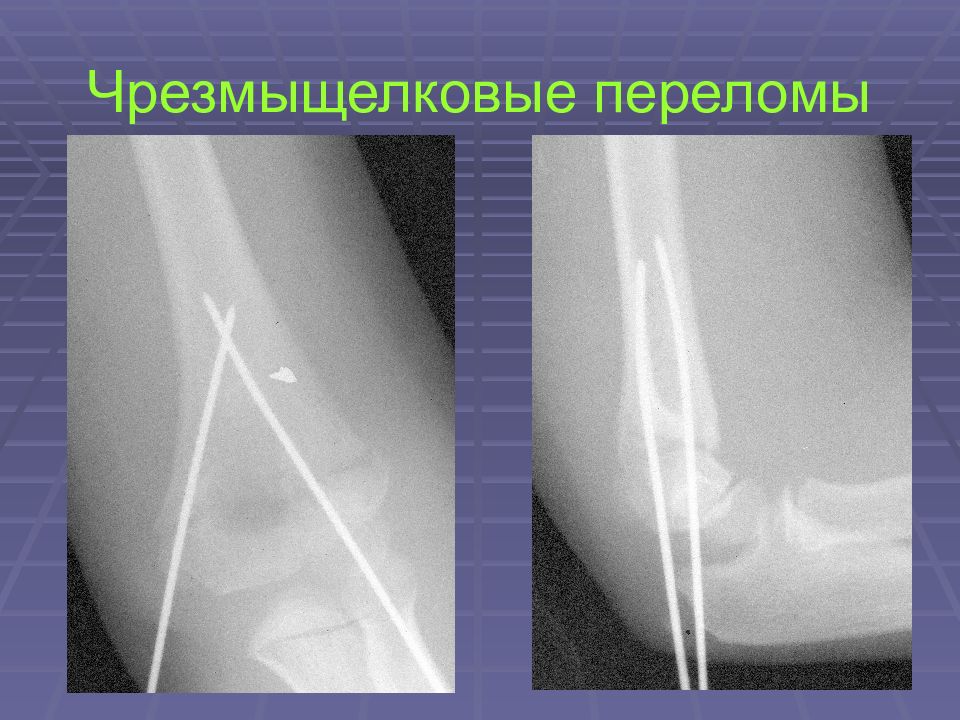

• Чрезмыщелковые переломы